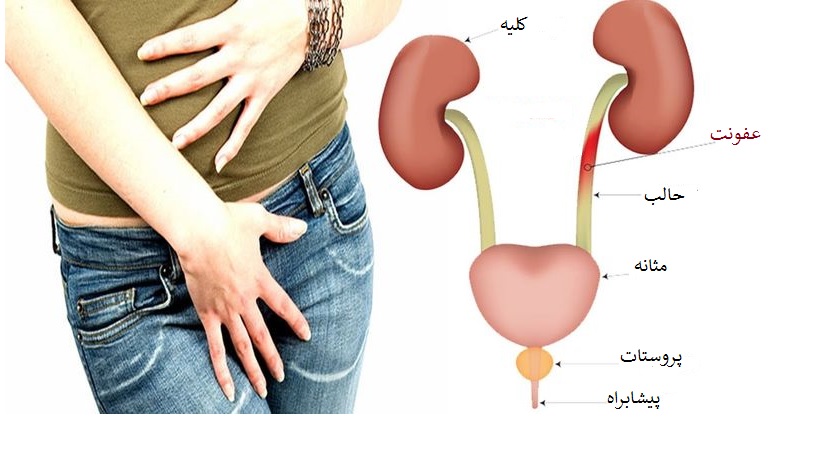

در هر ساعت کلیه های بدن انسان حدود ۷ لیتر مایع را از خون جدا می کنند این مایع را تصفیه کرده و مواد مفید و سودمند آن را به خون بازمی گردانند و مواد مضر آن را از راه میزنای به مثانه می فرستد تا دفع شوند. کجای بدنتان درد می کند مراجعه کنید آیا کلیه تان درد می کند درد کلیه در اثر عفونت کلیه یا آسیب رسیدن به آن ایجاد می شود. اما کار و وظیفه کلیه ها در بدن چیست بیا یاد بگیریم. زمانیکه کلیه ها بدرستی فعالیت کنند مواد زائد از بدن داخل ادرار ترشح می شوند همچنین کلیه ها در تنظیم سایر مواد معدنی در بدن مانند.

کلسیم و فسفر که برای تشکلی استخوان لازمند کمک می کنند مواد. کلیه ها با تولید ادارد در دفع مواد زاید تعادل الکترولیتی تنظیم هورمونی تنظیم فشار خون و هوموستازگلوکز نقش دارند. آناتومی کلیه انسان در بدن انسان به این شکل است که کلیه ها دو عضو لوبیایی شکل در دستگاه ادراری بوده و به دفع مواد زائد به صورت ادرار کمک می کنند. یکی از مهم ترین وظایفی که کلیه ها در بدن بر عهده دارند پاک کردن و تصفیه خون از زباله هاست.